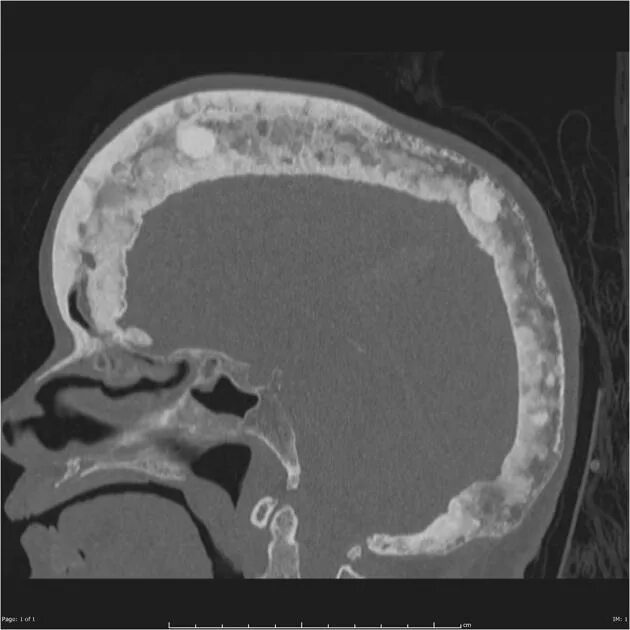

Заболевание кт